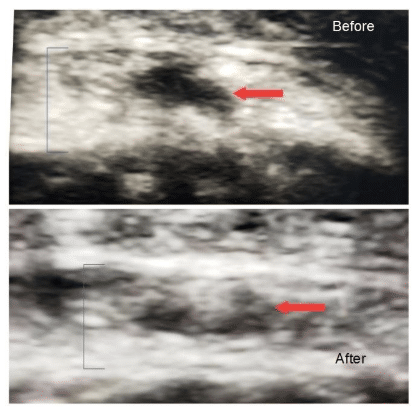

See below for a cross-sectional view of a patella tendon, thickness identified by bracket, before and after PRP injection. The black, also known as hypoechoic, is the area of chronic tendinitis and marked by the red area.